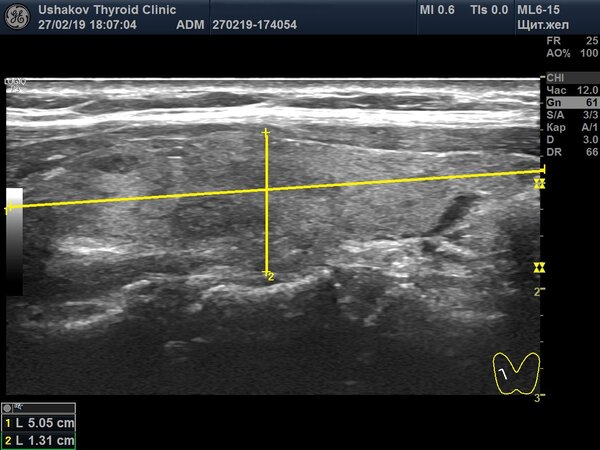

На изображении показана поперечная проекция правой доли. Жёлтыми линиями отмечены два ключевых измерения, а в левом нижнем углу можно увидеть их численные значения.

2. Продольная проекция. Затем врач измеряет длину доли — расстояние от верхнего до нижнего полюса.

На этом снимке продольной проекции также видны два измерения. В данном примере длина доли составила 50,5 мм, ширина — 13,8 мм, а наибольшая глубина — 13,1 мм.

Стоит отметить, что измерение длины может иметь погрешности. Например, из-за неправильного расположения датчика или если длина доли превышает размер самого датчика (часто его рабочая поверхность — 40 мм).